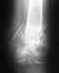

Как вы думаете поможет мне эндопротезирование? Делают ли такие операции у Вас?

В нашем инститте делают ндопротезирование голеностопного сустава. Чтобы решить, походит ли эта операция Вам, надо появиться на очную консультацию. Если эта операция в Вашем случае целесообразна, можно будет ее сделать по федеральной программе бесплатно (при наличии направления из местного Минздрава).